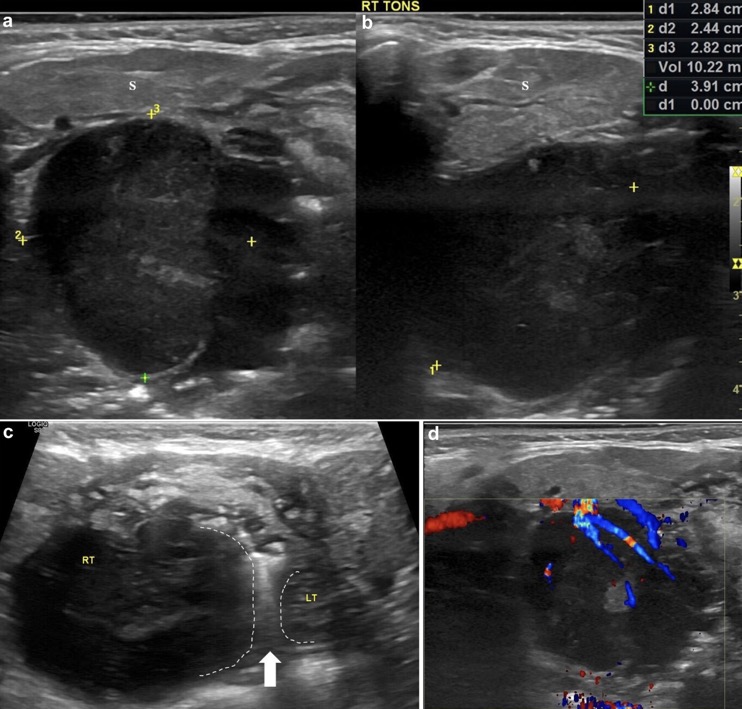

1. Asymétrie de la taille des amygdales (élargissement unilatéral)

2. Sphérique au lieu d'ovoïde

3. Altération de l'échotexture des amygdales

(A) Homogènement hypoéchogène

(B) Perte de son apparence striée

5. Capsule amygdalienne bien définie mais sans limites lobulées régulières

6. Tissus péritonsillaires normaux

EX: LYMPHOME DE BURKITT